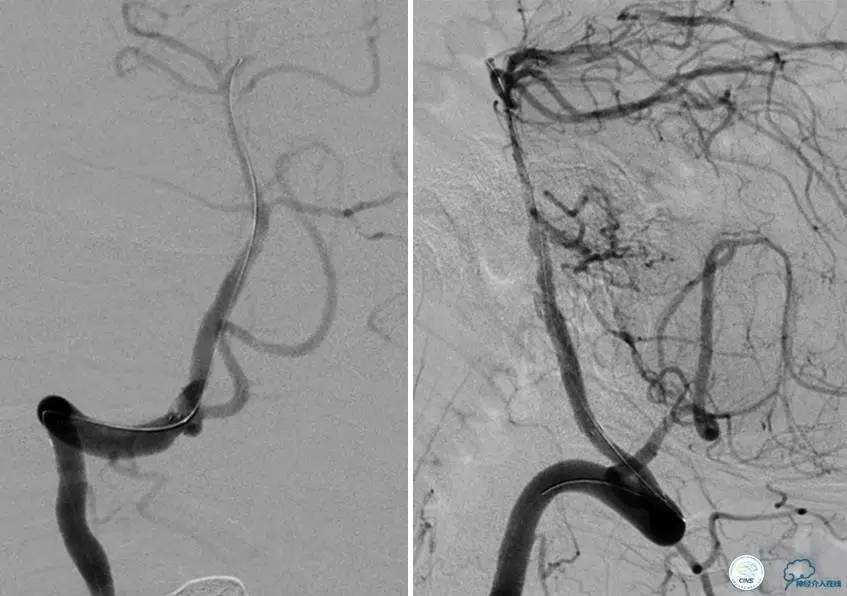

患者:49岁男性,左侧偏瘫1个月,药物治疗、康复训练效果不好,转我院,肌力0~1级。

core-clilnical明显不匹配,是介入开通的合适患者。

造影评价血管、判断闭塞段,微导丝谨慎穿过闭塞段,微导管造影,交换技术,球囊扩张,Enterprise支架。在后扩张时导丝刺破M3段血管,蛛网膜下腔出血(SAH)。

微导管进入破裂血管,栓塞弹簧圈1枚,出血停止,结束手术。继续双抗,术后2天肌力2级,神经功能恢复明显加快。

术后即刻和6天后CT,患者无明显临床症状。

半年后复查造影,无支架内再狭窄,可见弹簧圈,患者恢复至自己柱杖行走。